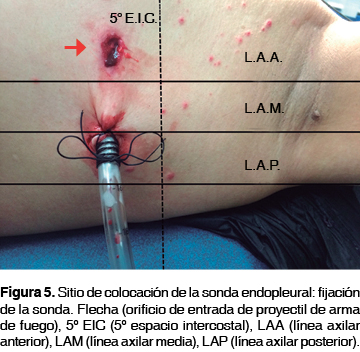

En todos los pacientes se emplearon sondas Argyle™ Thoracic Catheter Straight 32 Fr (10.7 mm) x 20" (51 cm) (figura 2), las cuales fueron colocadas entre las líneas axilar anterior y media en el quinto espacio intercostal (figuras 3 y 4), fijadas con seda 1 a la piel (figura 5) y conectadas a un sistema de drenaje torácico de tres cámaras Atrium™ Ocean Water Seal Chest 2002 Single Collection (figura 6) con succión continua a 20 cmH2O. Durante el procedimiento se les administró tramadol 100 mg por vía intravenosa e infiltró en el sitio de colocación con lidocaína al 2% con epinefrina a una dosis de 7 mg/kg, después se les proporcionó antibioticoterapia con ceftriaxona 1 g cada 12 horas por vía intravenosa durante el período de permanencia de la sonda y analgesia con ibuprofeno 400 mg cada ocho horas por vía enteral si estaba disponible la misma, hasta el retiro de la sonda; además, recibieron curación diaria del sitio de inserción de la sonda -consistente en lavado del sitio quirúrgico con iodopovidona y movilización gentil de la sonda, verificando su permeabilidad- bajo analgesia con tramadol y con posterior control radiográfico.